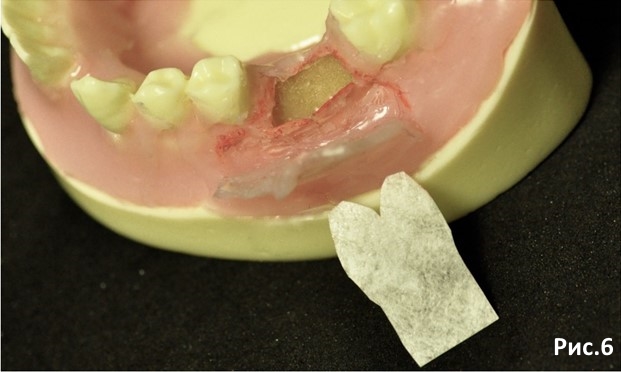

Выкраиваем мембрану под дефект. Обратите внимание на контуры. При такой форме она лучше укладывается в дефект и подшивается не образуя грубых складок. Рис.6